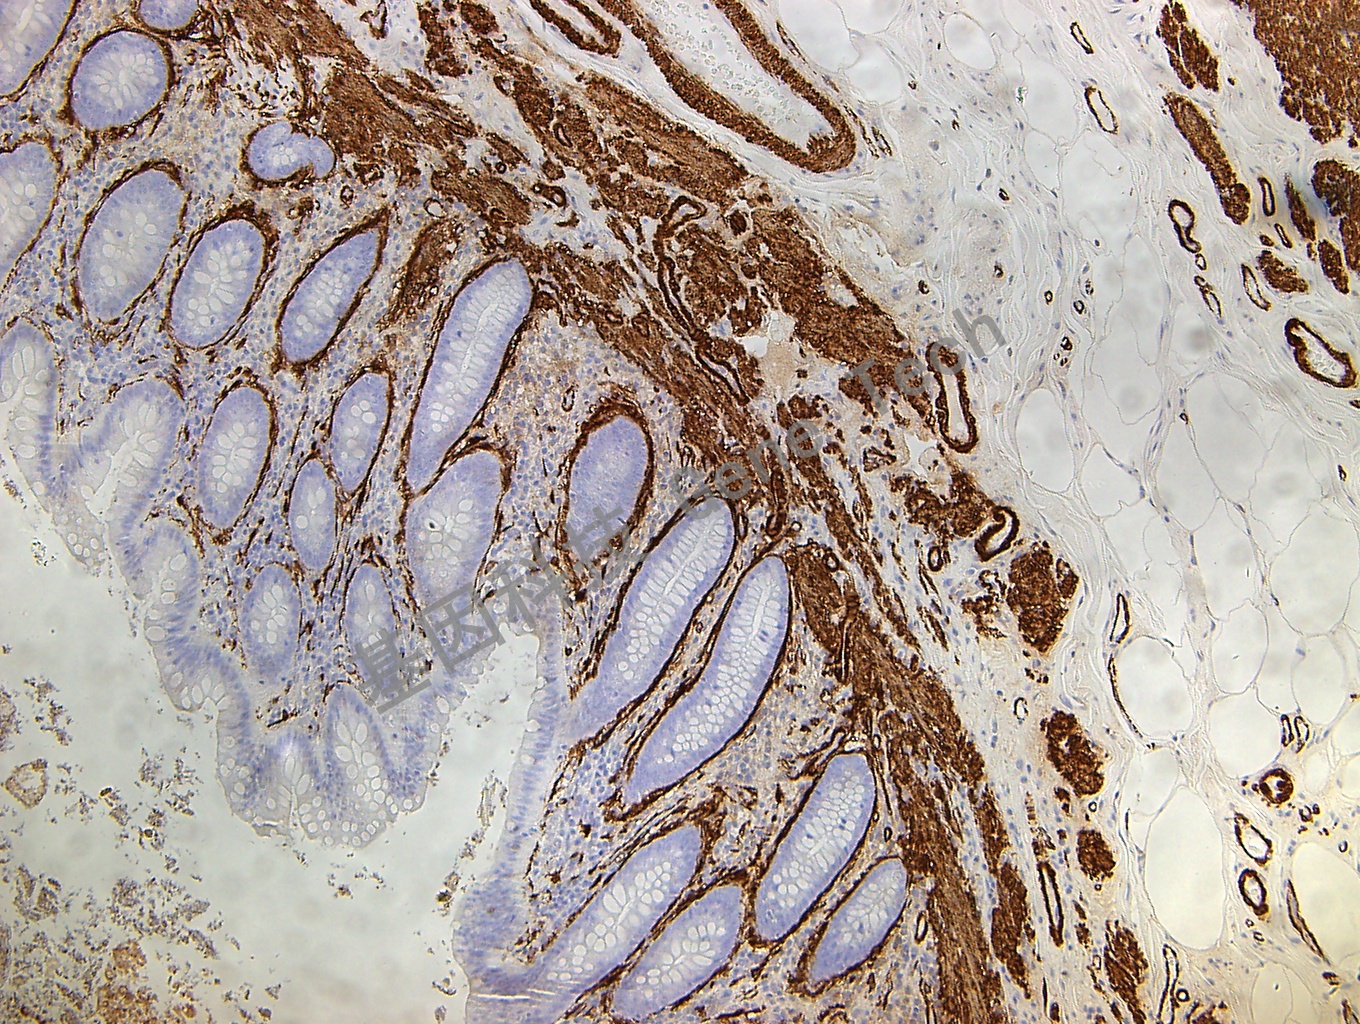

SMA 鼠抗人 SMA 抗體試劑(免疫組織化學(xué))

| 預(yù)處理:高pH熱修復(fù) | 陽性部位:細(xì)胞漿 | 陽性對照:闌尾 |

| 簡介:SMA(Smooth Muscle Actin, 平滑肌肌動蛋白)主要標(biāo)記平滑肌和肌上皮細(xì)胞。用于證實(shí)平滑肌瘤,乳腺、涎腺和汗腺的肌上皮細(xì)胞。 | ||

| 闌尾石蠟切片,用 SMA(GM0851)染色,細(xì)胞漿陽性,DAB 顯色。 | ||